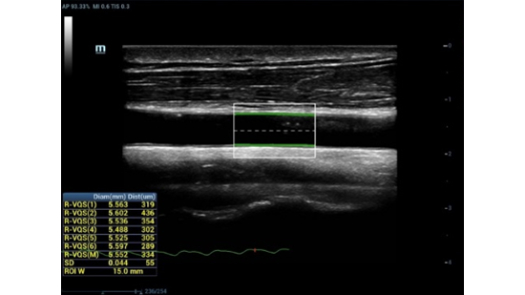

R-VQS

- Количественный анализ жесткости сосудов основан на радиочастотных данных и обеспечивает чрезвычайно точные расчеты растяжения сосудистой стенки

- Решение для ранней диагностики сердечно-сосудистых заболеваний

- После сбора данных нажмите «Полученные результаты», при этом создается отчет о PWV и коэффициенте твердости

- Высокая точность, измерение в реальном времени и автоматическое измерение обеспечивают универсальное решение для ранней диагностики сердечно-сосудистых заболеваний